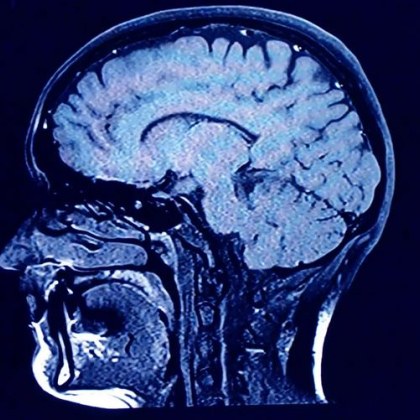

Учени разгледаха как смъртта влияе върху човешкия мозък и това

...... затворени очи и готови да ни напуснат, техните мозъци вероятно възпроизвеждат някои от най-прекрасните моменти, които са преживели през живота си,“ допълни още той.Превод: GlasNews.bg

Способността да превръщаме преживяванията в спомени ни дава възможност да

...... за нашето физическо и психическо здраве. Изследователите смятат, че трябва да се обърне специално внимание на мозъка, тъй като той претърпява свързани с възрастта промени.